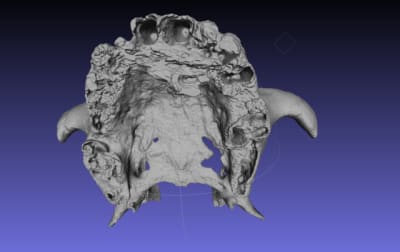

qu'est ce que vous pensez de ce guide, à mon avis il ne nécessite ni irrigation interne ni pins de rétention ( s'il est supra osseux) car rien qu'à l'aide d'un petit coup de marteau il s'enfoncera très bien sur l'Os avec une tres grande précision grace à sa structure trabéculaire.

Je vous invite à voir les autres images sur la Dropbox car elles sont très volumineuses et je n'ai pas pu les importer sur eugenol.